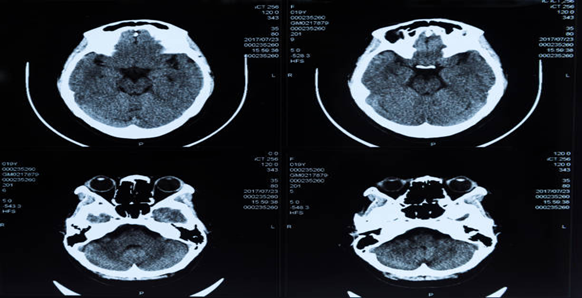

El diagnóstico de un hematoma óseo suele implicar una exploración física y pruebas de imagen, como radiografías, resonancias magnéticas o tomografías computarizadas. Estas pruebas pueden ayudar a evaluar la gravedad de la lesión y descartar otras afecciones. El tratamiento puede incluir reposo, hielo, compresión y elevación (RICE), inmovilización, fisioterapia o incluso cirugía, dependiendo de la localización y magnitud del traumatismo.

El diagnóstico de un hematoma óseo requiere un enfoque exhaustivo. Los profesionales médicos utilizan diversas técnicas y métodos para identificar con precisión este tipo de lesión. A menudo se emplean pruebas de imagen como radiografías, resonancias magnéticas y tomografías computarizadas para visualizar la zona afectada y determinar la gravedad del hematoma. Además, los reconocimientos físicos y los historiales médicos son fundamentales para el proceso, ya que permiten conocer las circunstancias que condujeron a la lesión y los síntomas experimentados. Además, las gammagrafías óseas, que implican la inyección de una pequeña cantidad de material radiactivo en el torrente sanguíneo, pueden ayudar a detectar la presencia de un hematoma óseo. Por último, la evaluación de los síntomas comunicados por el paciente también puede apuntar a un hematoma óseo, aunque es importante tener en cuenta otras posibles causas.

Como el diagnóstico de un hematoma óseo depende de un enfoque polifacético, los profesionales sanitarios deben adoptar una visión holística de la lesión. Utilizar una combinación de pruebas de imagen, exploraciones físicas e historiales médicos permite a los médicos hacer un diagnóstico preciso y desarrollar un plan de tratamiento eficaz. Al identificar la zona afectada y descartar cualquier fractura u otras afecciones, los profesionales médicos pueden determinar el mejor curso de acción para promover una rápida recuperación. Además, el uso de gammagrafías óseas permite a los médicos evaluar la gravedad de la lesión y detectar zonas de alta presión, como el aumento de presión, que pueden aportar información adicional sobre la lesión.

En conclusión, los profesionales médicos emplean diversos métodos para diagnosticar una contusión ósea. Combinando pruebas de imagen, exploraciones físicas, historiales médicos y gammagrafías óseas, los profesionales sanitarios pueden evaluar con precisión la lesión y elaborar un plan de tratamiento a medida. Este enfoque integral garantiza que el paciente reciba la mejor atención posible y pueda recuperarse totalmente.